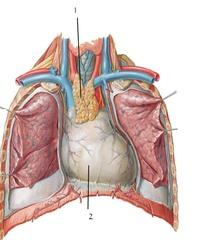

Bronchioles

Horizontal fissure (of right lung)

Internal/external intercostal muscle

Left/right oblique fissue (of lung)

Left/right primary bronchus/bronchi

Pleural cavity

Pleural membrane

Secondary bronchi

Trachae

Upper/middle/lower lobe (of lung)